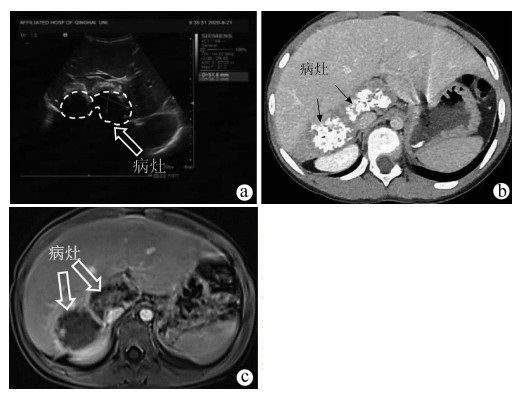

Complete resection of hepatic vesicular hydatid of caudate lobe in a child by midline fissure approach combined with left and right approaches: A case report

Han LI, Lizhao HOU, Haijiu WANG, Cong WANG, Haining FAN

2022, 38(2): 426-429. DOI: 10.3969/j.issn.1001-5256.2022.02.033

Abstract(1071) HTML (276) PDF (3527KB)(33)

Abstract: